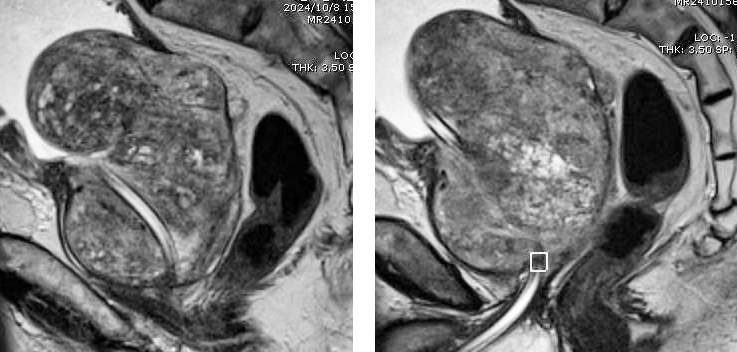

此次,患者因不愿長期留置尿管,要求行手術治療。前列腺MRI檢查示前列腺巨大,大小為351克,且合并膀胱多發結石。一般前列腺肥大手術患者大小多在20-100克,超過200克的病例較為罕見,此例患者臨床極為罕見,為我院開展前列腺手術最大體積前列腺。一般超大體積前列腺多采取開刀手術,可縮短手術時間,但開刀手術創傷大,術中術后出血較多,患者術后恢復慢,痛苦大,且存在膀胱漏尿,切口裂開等并發癥。